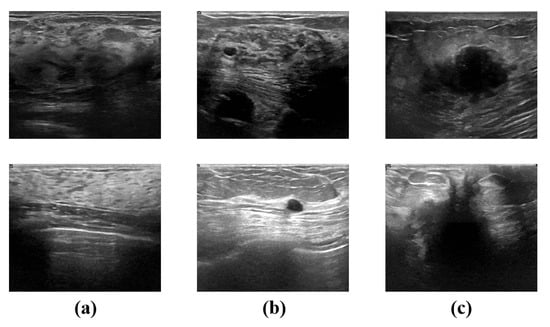

The methods for breast disease diagnosis mainly include clinician touch examination, radiological technology and cell histopathological biopsy. Benefiting from advances in imaging techniques, the accuracy of diagnosing breast lesions has improved significantly over the past few years. Among the advantages of non-invasive, radiological techniques, such as mammography, ultrasound, and computer tomography, have become essential and important procedures in the diagnosis of breast cancer. By using these technologies, abnormal signs in the breast can be effectively detected and located. Due to the characteristics of its practical inspection approach, cheap cost, no radiation, high real-time performance, and robust equipment mobility, ultrasound imaging has emerged as a key tool for early breast diagnosis and as an aid in the localization of minimally invasive breast rotational surgery [,]. Figure 1 presents normal, benign and malignant cases in the breast ultrasound dataset BUSI.

Figure 1.

Examples of images in dataset BUSI (first row) and dataset (second row). (a) shows an example of normal case images, (b) images with benign lesion and (c) examples with malignant lesion.